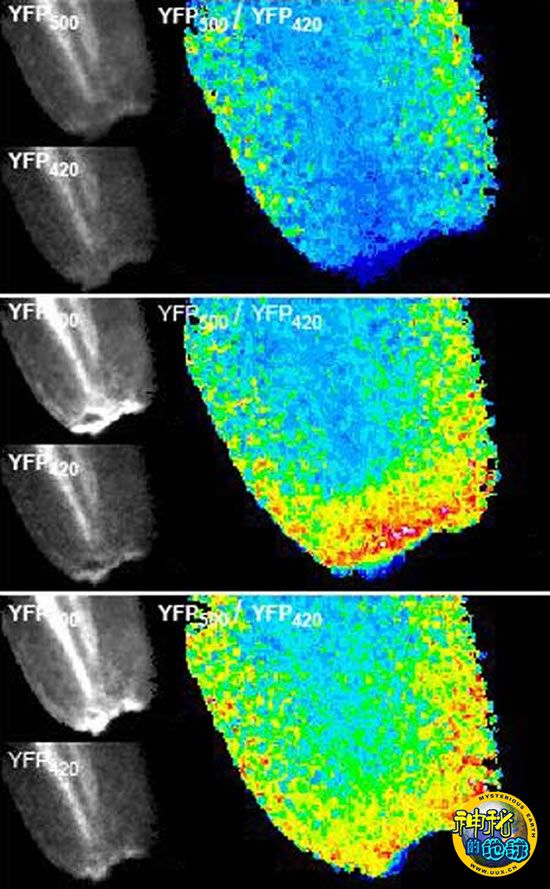

一条小斑马鱼的尾部在被割破后3分钟、17分钟和61分钟(由上至下)的图像,从中可以看到,过氧化氢从伤口释放,并随着向组织的扩散而不断褪色。

美国波士顿市哈佛医学院的博士后、生物学家Philipp Niethammer在注意到一些奇怪的现象后,决定尝试在斑马鱼受伤的尾部诱发一次过氧化氢的爆发。Niethammer说:“我在伤口发现了某些物质的爆发,但我在这里却没有找到白血球。”实验显示,这种爆发的物质是过氧化氢——它比白血球的出现平均早了17分钟,而人们通常认为,过氧化氢正是由白血球所形成的。就Niethammer看来,这似乎更像在说白血球是被过氧化氢带到伤口来的,而非是由白血球释放了过氧化氢。